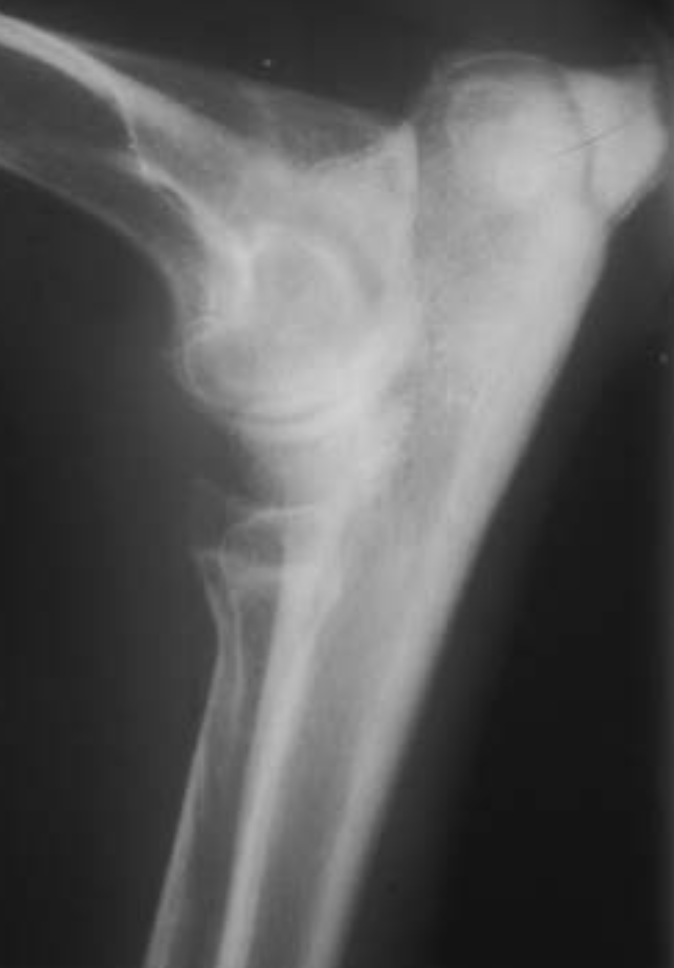

3.5m Yorkie

lateral humeral condylar fracture - see its caudal displacement, superimposed over the cranial ulna.